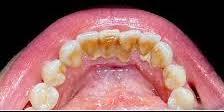

Scaling and root planing, also known as deep cleaning, is a non-surgical procedure performed by our experienced dental professionals to treat and prevent gum disease. It is typically recommended when gum pockets are deeper than normal or when there is evidence of plaque and tartar buildup below the gumline.